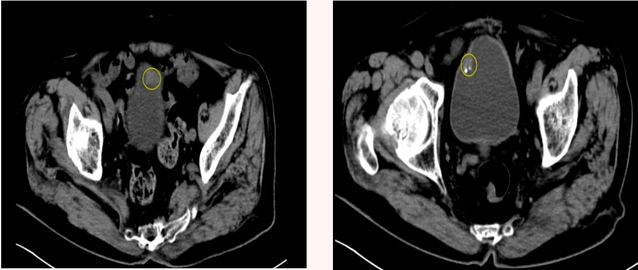

泌尿外科团队既要尽可能完美地解决梗阻又要最大限度缩短手术时长、减少术中损伤和出血。手术中发现膀胱肿瘤分布于膀胱前壁和顶壁,且肿瘤多发,较大直径约2.5cm,且位置较高,增加了手术难度,所幸凭借蒋民军娴熟的手术技巧、丰富的手术经验,成功地将所有肿瘤切除,并避免了其他器官的损伤,手术时间仅持续了25分钟。